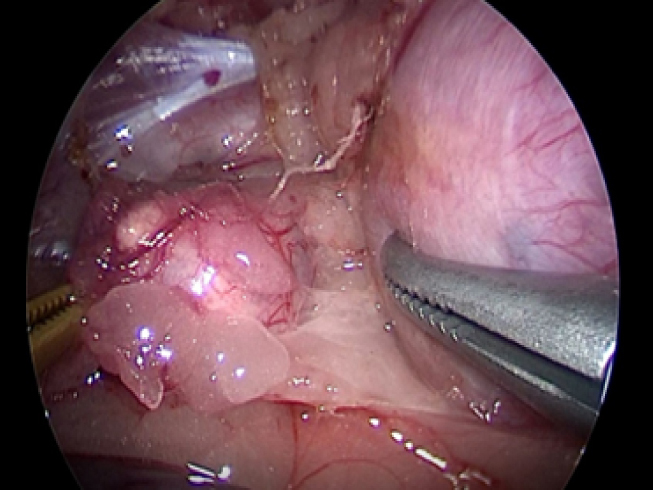

腎臓と副腎の間を剥離していきます。 ここでも腫瘍の周りには豊富に血管があるので丁寧に剥離していきます。

実際の手術風景です。

犬の右副腎2.5cm。腹腔鏡下手術。3ポートで摘出が可能。

CLARA&CROMAという新しいモードで手術している。

これは暗いところ明るくし、CROMAは赤を強くしコントラストをつけることにより血管一本までしっかりと確認することができる。

少しギラギラするが、手術しやすくなる。